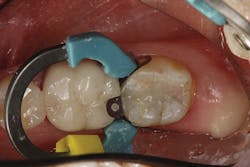

The contouring and primary anatomy can be placed with a flame-shaped fine diamond. Next, the occlusion is checked and refined on the restoration. Finally, the restoration can be polished easily with a two-step technique. I like to use polishing cups so I can polish both the occlusal and interproximal without having to change to a different polishing point. I first use Enhance (Dentsply Sirona), which can help shape as it polishes, and the final high shine is placed with the PoGo cup (Dentsply Sirona; figure 4).